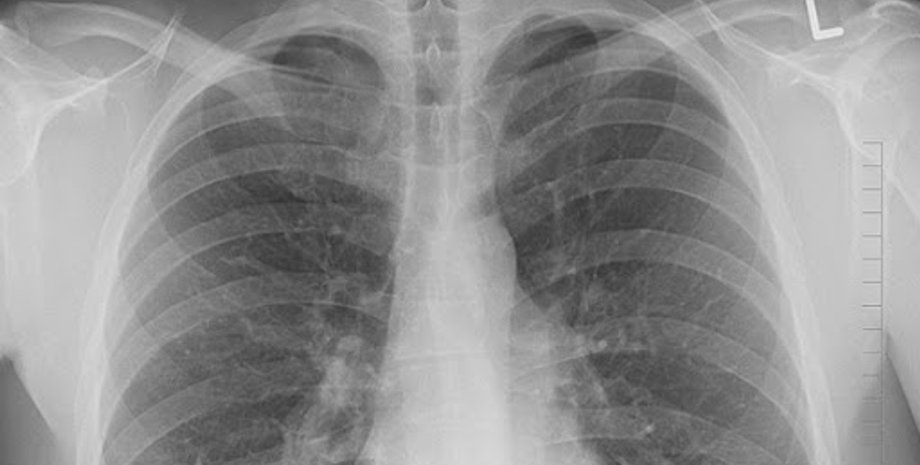

Фото: workingmama

За неделю количество пневмоний увеличилось в 5 раз по сравнению с недельной заболеваемостью в июле. Об этом сообщил глава Минздрава Максим Степанов на брифинге.

"Существенно увеличилось количество людей с пневмониями, за прошедшую неделю это 22 400 человек. Для понимания, например, в неделю с 13 по 19 июля всего было пневмоний 4 424, то есть более чем в 5 раз рост ", – сказал Степанов.